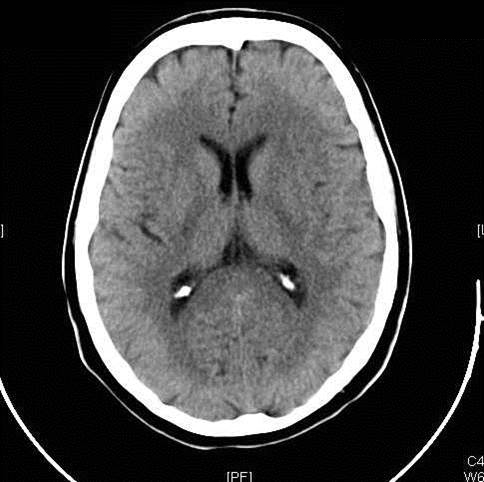

Figure 2: Hemorrhagic Stroke. The images below show a CT scan of a traumatic cerebrovascular injury, with a dissection of the right vertebral artery (left image) and a large stroke and intracerebral hemorrhage with midline shift on the right side of the brain (right image). (Images courtesy of Dr. McMurtrey)